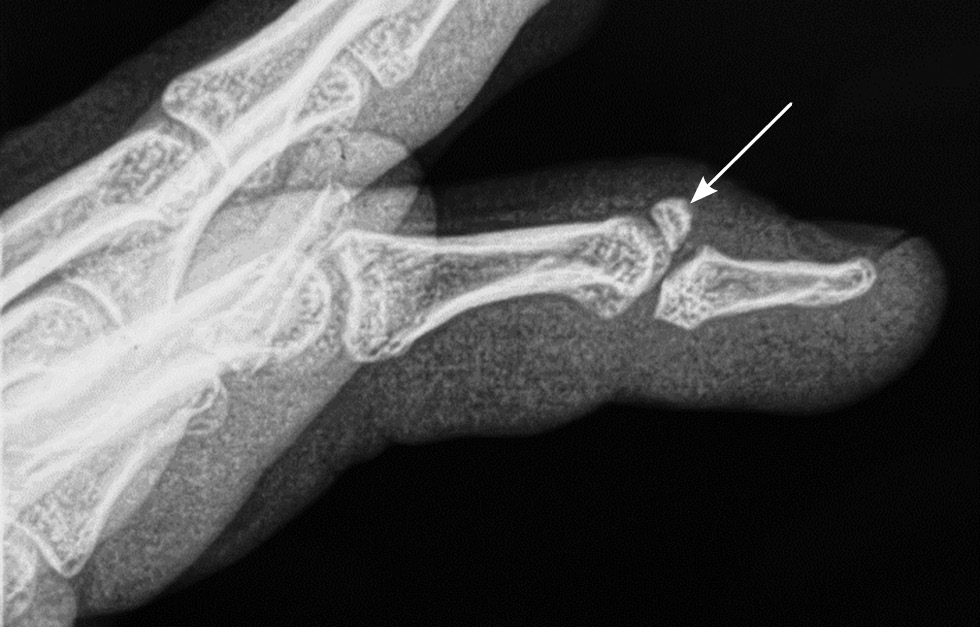

В исследование включали пациентов, соответствующих критериям: наличие авульсивного внутрисуставного перелома основания ногтевой фаланги пальца кисти со смещением более чем на 1/3 суставной поверхности (рис. 1), оперативное лечение в ранние сроки (до 14 сут с момента травмы).

Рис. 1. Рентгенограмма ребенка 14 лет с авульсивным переломом основания ногтевой фаланги (mallet fracture) III пальца правой кисти со смещением.